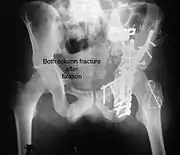

Combined both column fracturesThese are the most complex injuries. Here the weight bearing roof or dome of the acetabulum is a floating piece. This adds to complexity of management.

All three x-ray views plus CT scan is a must for diagnosis and management of this complex injury.

Treatment

Like any other acetabular fracture, if the femoral head is dislocated out of the socket, early reduction into socket is a priority. However, in this injury, non-operative treatment rarely gives satisfactory results. Surgical management is ideal. The choice of approach rests with the surgeon, but going from front, or anterior approach is must. The posterior injury may be tacked with anterior approach by experienced surgeon. If the patient is unfit to undergo major surgery due to any reason, longitudinal traction to achieve secondary congruence of hip may help to restore hip function, though partially.